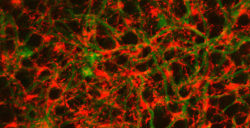

In addition, the retina contains a special type of adult stem cell, called Müller glia, that span all three layers and provide mechanical support and electrical insulation. In fish retinas, they also play a key role in regeneration. When regeneration is triggered, the Müller glia dedifferentiate (regress from a specialized state to a simpler state), begin proliferating, and then differentiate into replacements for the damaged nerve cells. Müller glia are also present in mammalian retinas, but don’t regenerate.

So, working with Patton and research assistant professor Dominic Didiano, Rao designed a series of experiments with zebrafish – an important animal model for studying regeneration – which determined that high concentrations of GABA in the retina keep the Müller glia quiescent and that they begin dedifferentiating and proliferating when GABA concentrations drop.

On the other hand, when they injected an enzyme that lowers GABA levels in the eyes of normal fish, they found that the Müller glia began dedifferentiating and proliferating, the first stage in the regeneration process.